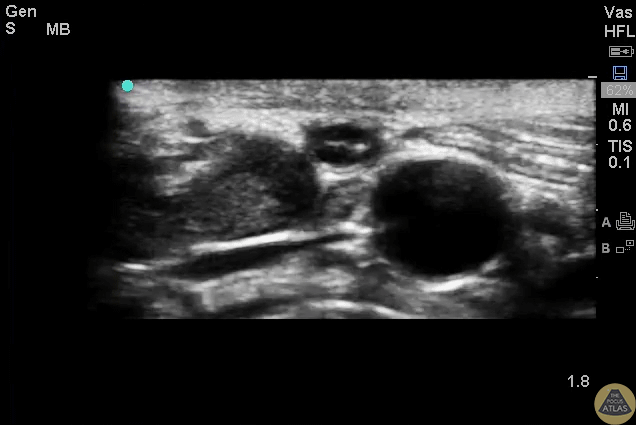

Normal appendix with landmarks including the psoas, ilac artery/vein, and the appendix. Images provided by Sathya Subramaniam - Children’s Hospital of Philadelphia, edited by Matthew Riscinti - Kings County Emergency Medicine